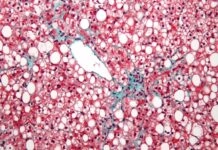

Τα αναψυκτικά διαίτης ίσως καταστρέφουν σιωπηλά το ήπαρ

Μεγάλου εύρους μελέτη έδειξε ότι τα άτομα που καταναλώνουν σε τακτική βάση τόσο αναψυκτικά με ζάχαρη όσο και light αναψυκτικά αντιμετωπίζουν σημαντικά αυξημένο...